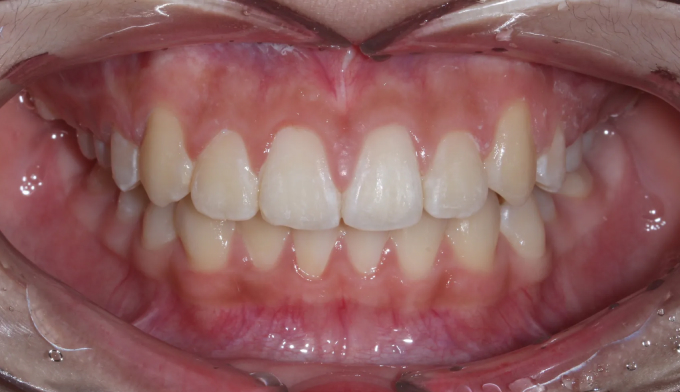

송곳니가 나올 공간이 전혀 없어 보입니다.(화살표로 표시한 부분이 송곳니가 나와야 할 공간입니다)

치아교정은 바른 교합을 형성하는것이 중요한 목적이기 때문에 윗니와 아랫니를 모두 교정하는것이 올바른 방법이지만, 특수한 경우에 있어서는 한쪽만 교정을 진행하는 경우도 있습니다.

위와 같은 경우는 환자 개인적인 사정으로 윗니만 교정한 경우입니다.

안모를 고려하여 앞니가 앞으로 뻗치지 않게 주의하면서 어금니만 후방이동시켜 송곳니가 맹출할 공간을 만듭니다.

총 교정기간은 13개월이 소요되었습니다.